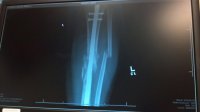

Was that taken during surgery or have you broken it before?Found the pic I took of my X-ray from my leg, this is from 2 months ago, it was snapped in a couple spots further down tooView attachment 8806

thats a month and a half after surgery, they put in that rod and left the other bone crooked, according to the doctor that was "healing nicely"

), but how is that "healing nicely"? Granted it looks like the bone is growing together, but how can it be strong if it isn't even remotely lined up?

Ok I'm not a doc (I did sleep at a Holiday Inn Express though), but how is that "healing nicely"? Granted it looks like the bone is growing together, but how can it be strong if it isn't even remotely lined up?

Hmm I guess this happens quite a bit. Here's another one post op.They're excuse was that the crooked bone (the fibula) isnt a weight bearing bone so it doesnt matter that it's not lined up, they went on about how with some patients they'll remove that bone entirely to reconstruct a busted jaw.

Of course they also said because of a medical condition I have laying down the bike again could cause it to break. I said "well maybe you'll fix it right next time."